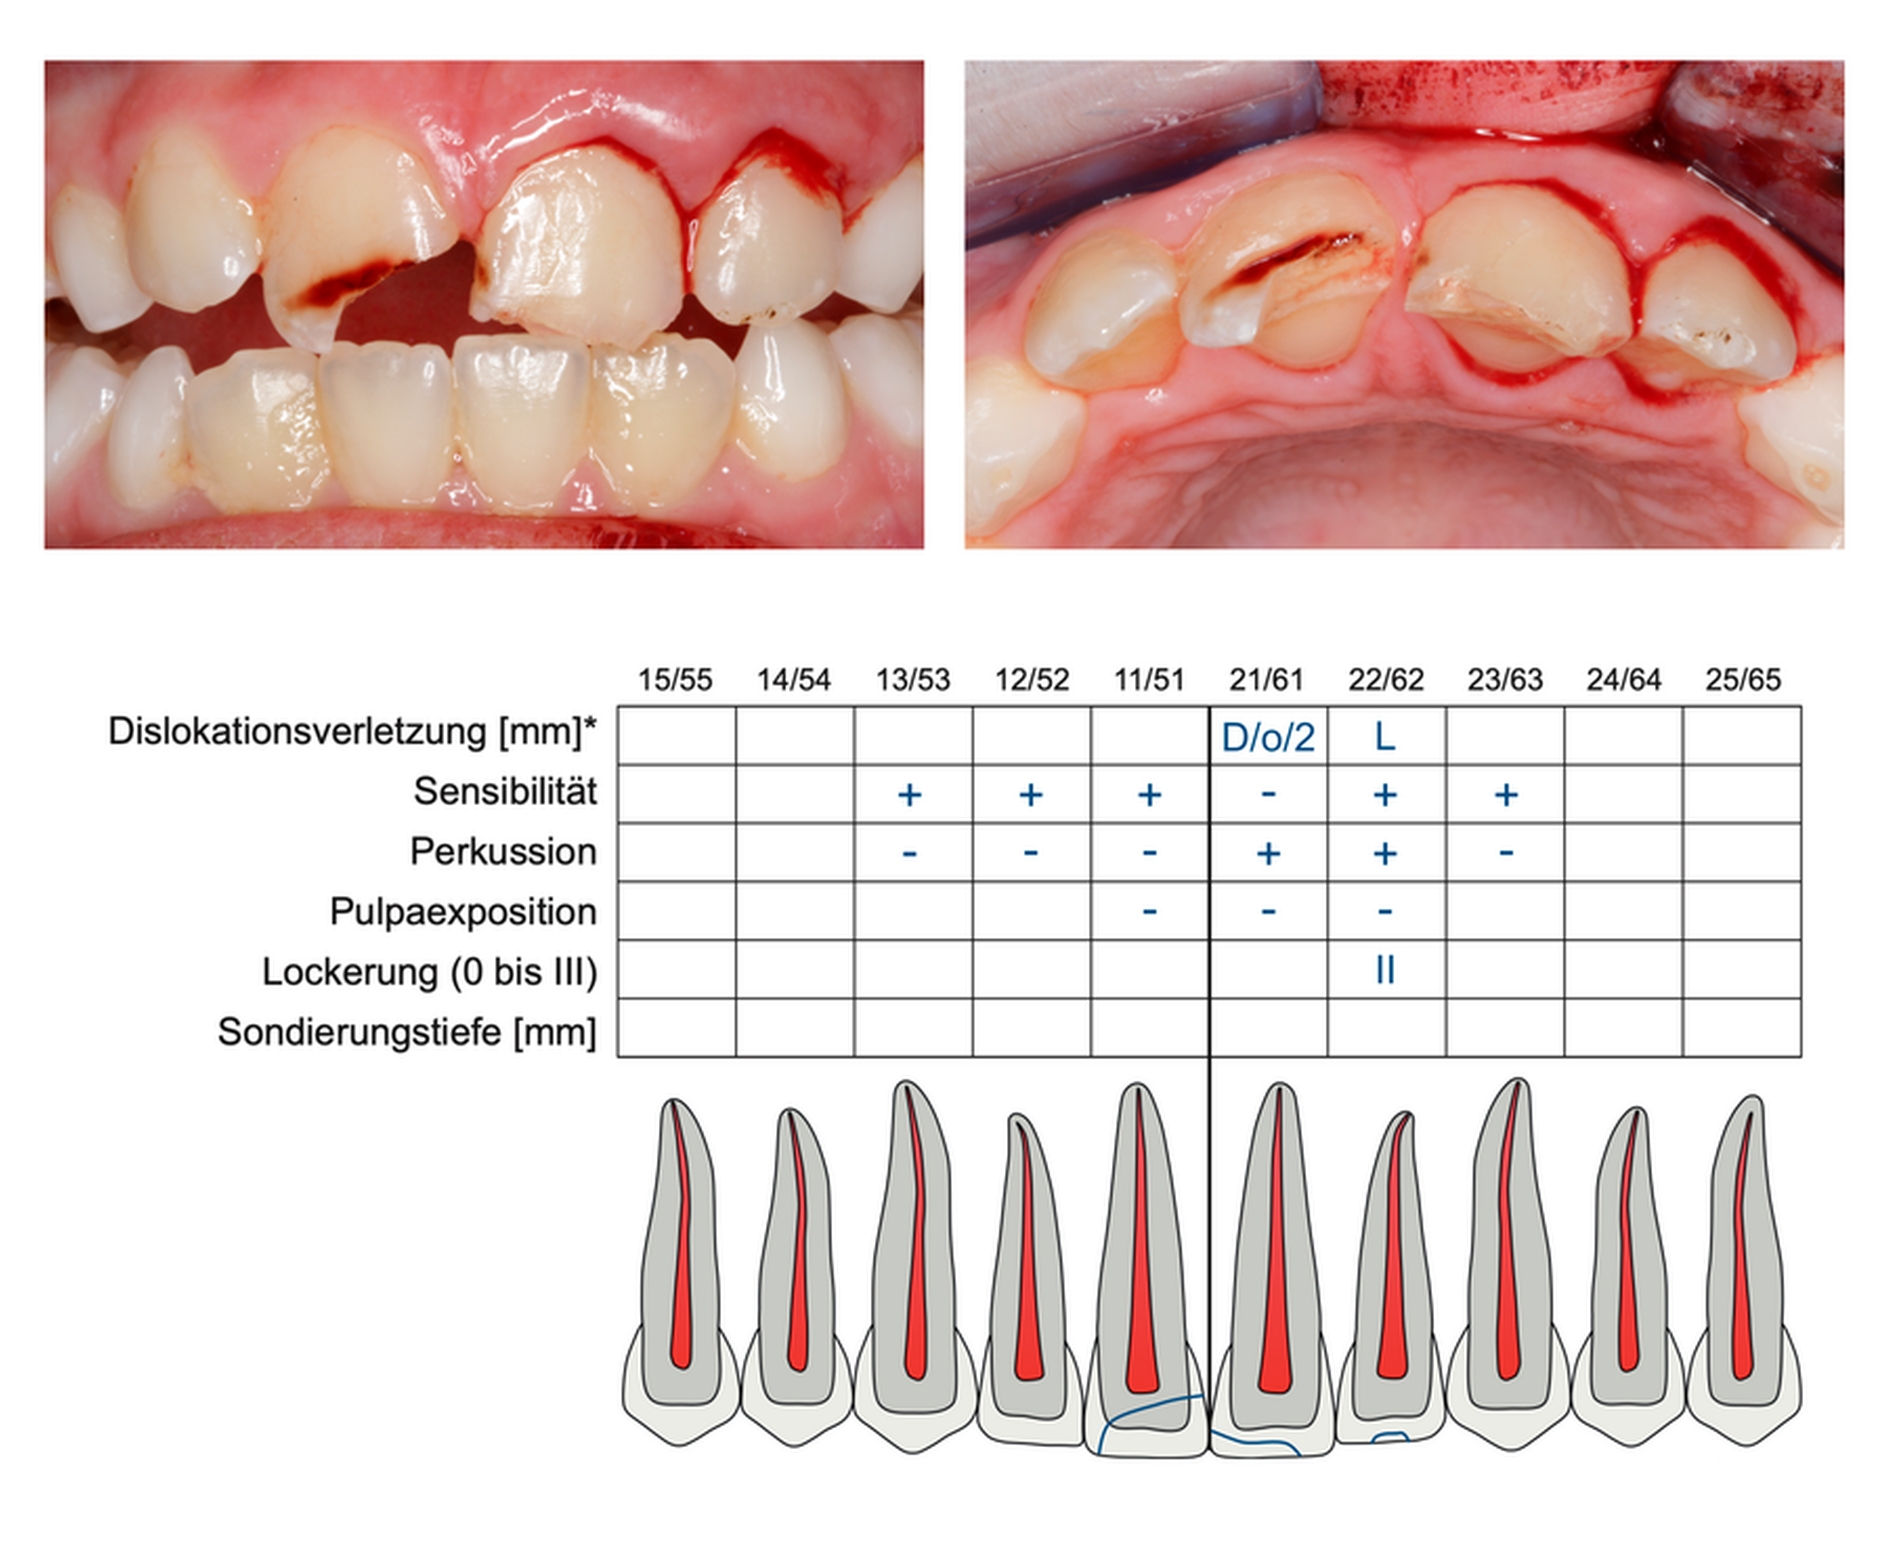

Da eine lückenlose Dokumentation die Grundlage für jede weitere Therapie bildet, stellen die Deutsche Gesellschaft für Zahn-, Mund- und Kieferheilkunde (DGZMK) und die Deutsche Gesellschaft für Endodontologie und zahnärztliche Traumatologie (DGET) ein einheitliches Erfassungsformular online zur Verfügung, das zudem als Leitfaden für die Anamnese und Untersuchung dient (Abbildung 5).

Zur Dokumentation dentaler Verletzungen steht ein Zahnschema zur Verfügung. Frakturverläufe können dort unter Berücksichtigung der beteiligten Gewebe (Schmelz, Dentin, Pulpa) eingezeichnet werden. Die Tabelle im Befundbogen bietet zudem die Möglichkeit, Dislokationsverletzungen zu dokumentieren, wobei hier die Art der Dislokation und gegebenenfalls das Ausmaß und die Richtung der Dislokation eine entscheidende Rolle spielen. Sowohl Frakturverläufe als auch Dislokationen lassen sich somit auch nach der Restauration beziehungsweise Repositionierung noch zweifelsfrei nachvollziehen. Außerdem sollten in der Tabelle Informationen bezüglich der Sensibilität, Schmerzen bei Perkussion, des Lockerungsgrades hinterlegt werden. Auf der Rückseite des Erfassungsbogens sollte man im Falle avulsierter Zähne angeben, wie lange diese initial trocken gelagert waren und in welcher Form sie transportiert wurden (Medium und Dauer). Diese Informationen sind nach der Replantation für die weitere Planung und Einschätzung der Prognose essenziell. Im Anschluss an die Avulsionsanamnese gibt es die Möglichkeit, spezielle radiologische Befunde festzuhalten. Entsprechend der Untersuchungsreihenfolge werden zuletzt noch weitere Befunde überprüft im Hinblick auf Hartgewebsschäden (Alveolarknochen), funktionelle Einschränkungen (Kiefergelenk) und Weichgewebsverletzungen (Mukosa, Lippen, Gesichtshaut).

Zur Dokumentation wird auch die Erstellung klinischer Fotos im Rahmen der Erstversorgung vor Therapiebeginn empfohlen. Gerade bei Dislokationsverletzungen geben Fotos oft wichtige Hinweise auf die Art und den Schweregrad der Zahnverlagerung, was maßgeblichen Einfluss darauf hat, ob eine endodontische Behandlung initiiert werden muss. Diese Information ist nach der Repositionierung des Zahnes nicht mehr vorhanden und kann auch auf dem Röntgenbild oftmals nicht genau beurteilt werden. Im optimalen Fall werden vor der Erstversorgung auf dem Behandlungsstuhl hochwertige Dentalaufnahmen von labialer und inzisaler Richtung aufgenommen. Gleichwohl können auch selbst erstellte Fotos oder Selfies wertvolle Informationen liefern. Neben der forensischen Dokumentation ist es durch Bildmaterial vom Unfalltag auch möglich, Zahnverfärbungen oder die Heilung von Weichgewebswunden nachzuvollziehen (Abbildung 6). Im Zuge der Nachkontrollen erleichtern fotografische Aufnahmen zudem die Feststellung von Infrapositionen bei Ankylosen oder die spontane Eruption bei Intrusionsverletzungen.

Die Fotodokumentation stellt eine hilfreiche Technik dar, da sie eine Ergänzung der Befunde erlaubt und die Klassifikation der Art des Traumas erleichtern kann. Sie sollte vor allem aus forensischen Gründen (Haftungs-Gesichtspunkte) eingesetzt werden und von labial und von inzisal am Unfalltag vor der weiteren Therapie erfolgen (Empfehlung 6).